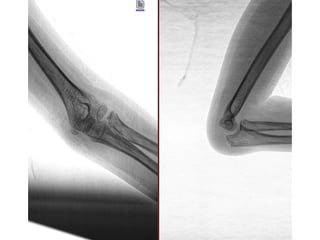

Diagnósticos: ARTRITIS REACTIVA PB ARTRITIS SEPTICA DE CODO IZQUIERDO

Cirugía Proyectada: PUNCION BAJO SEDACION VS ARTROTOMIA EVACUADORA DE CODO IZQUIERDO

Material OSS Solicitado: CLAVILLOS K

• 16.

NOMBRE:GARCIA CASTRO ABDIISRAEL SANTIAGO NSS:2007800269 3M2015OR URGENCIAS A Edad: 10 AÑOS Comorbilidades: NINGUNA Fecha de la lesión: 20/09/25 Mecanismo de lesión: SUBITO Laboratorios: DENTRO DE NORMALIDAD Valoraciones: NA Diagnósticos: ARTRITIS REACTIVA PB ARTRITIS SEPTICA DE CODO IZQUIERDO Cirugía Proyectada: PUNCION BAJO SEDACION VS ARTROTOMIA EVACUADORA DE CODO IZQUIERDO Material OSS Solicitado: CLAVILLOS K